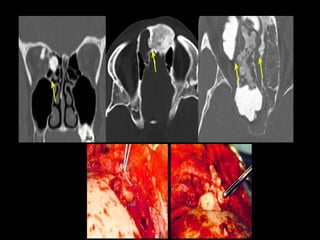

• Coronal section, contrast-enhanced computed tomography scan shows a large

heterodense destructive soft tissue lesion with intense contrast enhancement on the

right maxillary antrum (yellow arrow), crossing the midline and displacing the nasal

septum to the left (red arrow) and superiorly into the nasal cavity (blue arrow)

• contrast-enhanced computed tomography scan shows a large heterodense destructive soft

tissue lesion seen in the superior postero-lateral wall of the right nasal cavity, extending

into the nasopharynx and adjacent pterygopalatine fossa, right pre-maxillary space causing

bowing of the posterior antral wall: The characteristic Holman Miller sign (yellow arrow)

with erosion/ destruction of adjacent bones.